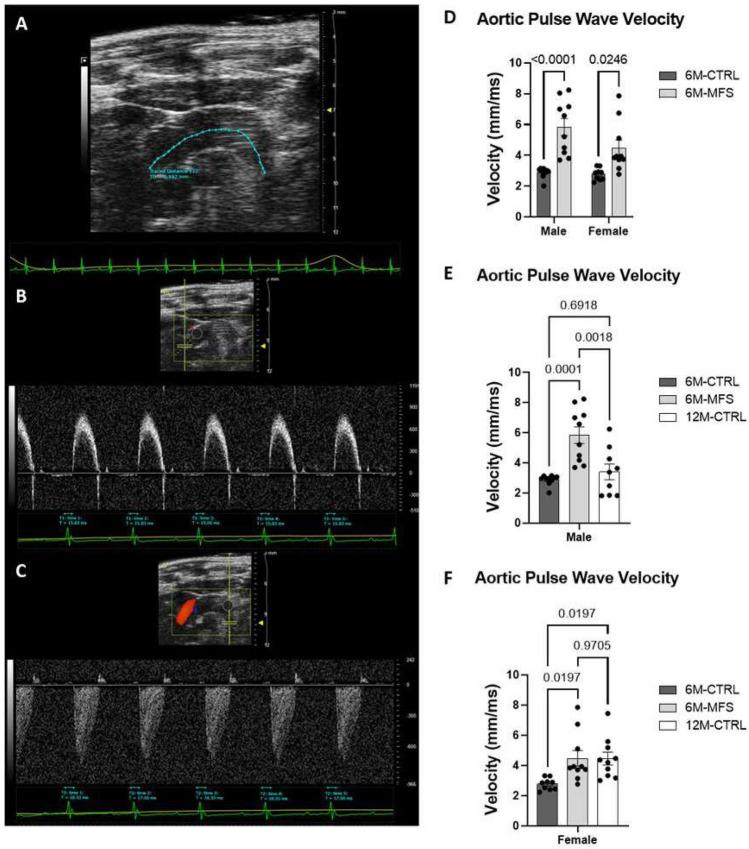

In individuals with Marfan Syndrome (MFS), fibrillin-1 gene (FBN1) mutations can lead to vascular wall weakening and dysfunction. The experimental mouse model of MFS (Fbn1) has been advantageous in investigating MFS-associated life-threatening aortic aneurysms. It is well established that the MFS mouse model exhibits an accelerated-aging phenotype in elastic organs like the aorta, lung, and skin. However, the impact of Fbn1 mutations on the in vivo function and structure of various artery types with the consideration of sex and age, has not been adequately explored in real-time and a clinically relevant context. In this study, we investigate if Fbn1 mutation contributes to sex-dependent alterations in central and cerebral vascular function similar to phenotypic changes associated with normal aging in healthy control mice. In vivo ultrasound imaging of central and cerebral vasculature was performed in 6-month-old male and female MFS and C57BL/6 mice and sex-matched 12-month-old (middle-aged) healthy control mice. Our findings confirm aortic enlargement (aneurysm) and wall stiffness in MFS mice, but with exacerbation in male diameters. Coronary artery blood flow velocity (BFV) in diastole was not different but left pulmonary artery BFV was decreased in MFS and 12-month-old control mice regardless of sex. At 6 months of age, MFS male mice show decreased posterior cerebral artery BFV as compared to age-matched control males, with no difference observed between female cohorts. Reduced mitral valve early-filling velocities were indicated in MFS mice regardless of sex. Male MFS mice also demonstrated left ventricular hypertrophy. Overall, these results underscore the significance of biological sex in vascular function and structure in MFS mice, while highlighting a trend of pre-mature vascular aging phenotype in MFS mice that is comparable to phenotypes observed in older healthy controls. Furthermore, this research is a vital step in understanding MFS's broader implications and sets the stage for more in-depth future analyses, while providing data-driven preclinical justification for re-evaluating diagnostic approaches and therapeutic efficacy.

在马凡综合征(MFS)患者中,原纤维蛋白 1 基因(FBN1)突变可导致血管壁弱化和功能障碍。MFS 的实验小鼠模型(Fbn1)在研究与马凡综合征相关的危及生命的主动脉瘤方面具有优势。众所周知,MFS 小鼠模型的主动脉、肺和皮肤等弹性器官表现出加速衰老表型。然而,Fbn1 突变对不同类型动脉的体内功能和结构的影响,在实时和临床相关的背景下,尚未得到充分探讨。在这项研究中,我们研究了 Fbn1 突变是否导致中央和脑血管功能的性别依赖性改变,类似于与健康对照小鼠正常衰老相关的表型变化。对 6 月龄雄性和雌性 MFS 及 C57BL/6 小鼠以及年龄匹配的 12 月龄(中年)健康对照小鼠的中央和脑血管进行了体内超声成像。我们的研究结果证实了 MFS 小鼠的主动脉扩张(动脉瘤)和壁僵硬,但在雄性中更为严重。舒张期冠状动脉血流速度(BFV)没有差异,但 MFS 和 12 月龄对照小鼠的左肺动脉 BFV 下降,无论性别如何。在 6 月龄时,与年龄匹配的雄性对照组相比,MFS 雄性小鼠的大脑后动脉 BFV 降低,但雌性组之间没有差异。MFS 小鼠无论性别如何,二尖瓣早期充盈速度均降低。MFS 小鼠还表现出左心室肥厚。总之,这些结果强调了生物学性别在 MFS 小鼠血管功能和结构中的重要性,同时突出了 MFS 小鼠中血管提前衰老表型的趋势,与老年健康对照者观察到的表型相似。此外,这项研究是理解马凡综合征更广泛影响的重要一步,为更深入的未来分析奠定了基础,并为重新评估诊断方法和治疗效果提供了基于数据的临床前依据。